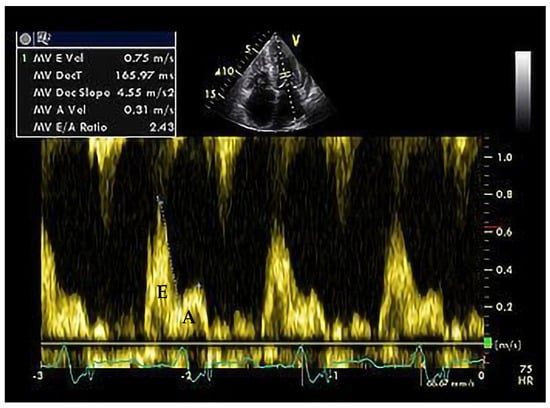

7. Restrictive Cardiomyopathy (RCM)